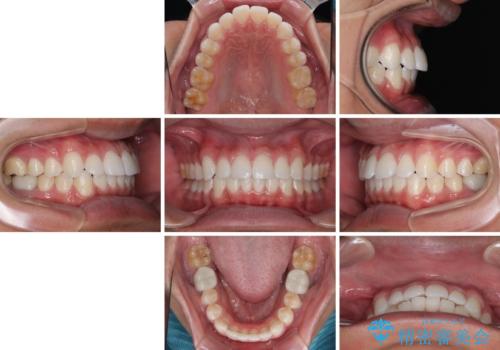

あっという間に歯列が整い、目立っていた銀歯もなくなり、清潔感のある口元になりました。